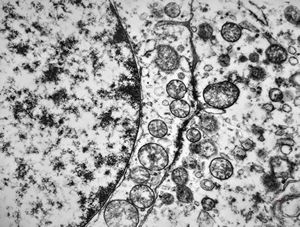

F,50y. | progressive multifocal leukoencephalopathy- viral particles in a glial cell